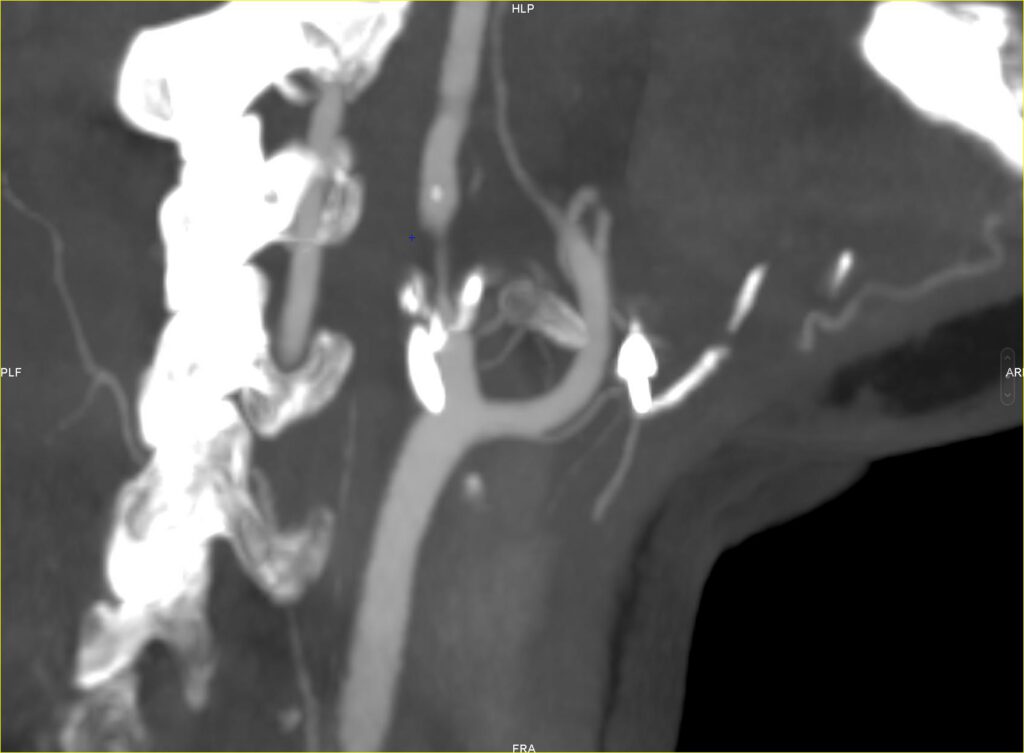

Après une ponction artérielle (piqûre), un cathéter (petit tuyau souple) est introduit soit dans l’artère fémorale commune droite au niveau du pli de l’aine soit dans l’artère radiale au niveau du poignet. Un cathéter est ensuite dirigé en temps réel sous guidage radiologique vers l’artère carotide pathologique. Une cartographie des artères carotides (artériographie) est alors réalisée en injectant du produit de contraste par le cathéter afin de bien évaluer l’étendue et le degré de rétrécissement de la carotide et réaliser ainsi un planning opératoire précis (zone d’inflation du ballon et de mise en place du stent).

On passe alors la sténose (rétrécissement) avec le cathéter puis on réalise alors soit directement la mise en place du stent (angioplastie stenting), soit il est parfois nécessaire réaliser une prédilatation au ballon (angioplastie au ballon) avant de mettre en place le stent. On réalise enfin une dernière artériographie pour confirmer la bonne efficacité de l’intervention. L’anesthésie est alors diminué et le patient est transféré en salle de réveil.